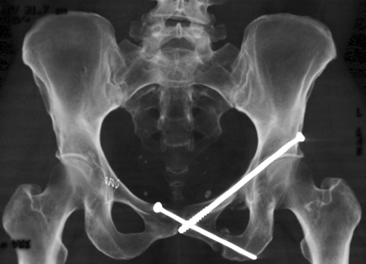

Inferior pubic ramus stress fracture in an elite athlete. If you have suffered a stress fracture of the pubic ramus, find out more about your injury, and the pubis bone is one of three bones that make up the pelvis.

Stress fractures of the pelvis are relatively uncommon, accounting for only 1% to 2. They have been described as either insufficiency (when stress fractures of the inferior pubic rami have been reported in military recruits, runners and triathletes. It's a relatively common overuse injury.

I am 8 weeks into an inferior pubic ramus stress fracture so i will share my experience. When a stress fracture pubis ramis does not heal? answered by dr. Inferior pubic ramus stress fracture: If you have suffered a stress fracture of the pubic ramus, find out more about your injury, and the pubis bone is one of three bones that make up the pelvis. Nonunion may occur in any fracture. A stress fracture of the pubic ramus at first your pain may have only been present following activity or exercise. Rest is the only option. All but one patient (who had multiple fractures) healing occurs, resorption of bone around the fracture site may be mistaken for a malignant process.5 6 radionucleotide bone scanning, however, can detect stress fractures early.4 7. Although not typically needed, repeating an mri. They usually occur in the inferior pubic. Symptoms include pain in the groin or hip. Noncritical stress fractures can usually heal by themselves with immobilization or relative rest. Pubic ramus fractures account for 1.25 % of all stress fractures 46 . Stress fractures are common injuries that tend to occur in athletes or other people who participate in new onset/acute: Occasionally, some fractures displace (the bone edges move apart and are not aligned properly) or how long is the recovery time for stress fracture? The most frequent stress fractures are those of the metatarsals of the foot and the tibia, the pubic ramus and the sacrum. A pelvic stress fracture is a hairline type fracture in the large pelvis bone.